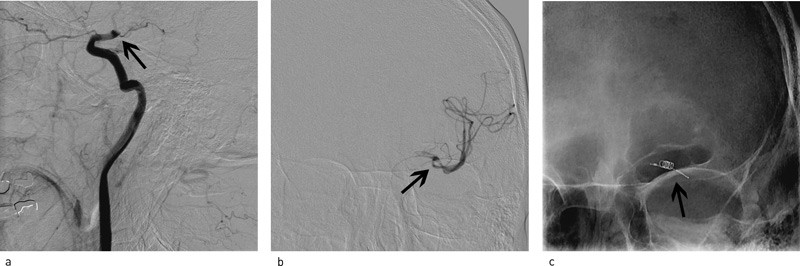

Ved cerebral angiografi fant man at det forelå en 90 % distal venstresidig stenose i a. carotis interna med redusert blodgjennomstrømming av venstre hjernehalvdel (fig 1a). Angiografisk bedømt forelå det få kollateraler og forsinket blodgjennomstrømming i venstre cerebrale hemisfære via a. comunicans anterior og a. comunicans posterior. Det var indikasjon for angioplastikk av stenosen. Ved bruk av ballongkateter (Maverick II) ble stenosen dilatert. Angiografisk ble reststenosen beregnet til 46 % (fig 1b). Etter ett døgn i intensivavdeling og to dager i slagavdeling ble pasienten utskrevet til hjemmet med uendret platehemmende medikasjon. Han var da symptomfri og uten svakhet i høyre hånd. Ved poliklinisk kontroll fire måneder senere var han fortsatt symptomfri, og blodtrykket var spontant normalisert.

Diagnostisk cerebral angiografi ble utført og pasientens basilarisstenose (fig 2a) samt den kollaterale sirkulasjonen ble evaluert. Det var minimal kollateral blodforsyning fra fremre kretsløp. Det ble gjort tre forsøk med angioplastikk (Maverick II-ballongkateter). Dette ga ikke tilstrekkelig blodstrøm i distale a. basilaris. Man la derfor en Wingspan-stent (Boston Scientific) i stenosen. Stenten bidro til forbedret blodstrøm til det distale basilariskretsløpet. Angiografisk reststenose ble målt til 50 % (fig 2b). Pasienten lå ett døgn i intensivavdeling etter prosedyren før han ca. en uke senere ble utskrevet til hjemmet med mild bilateral dysmetri i overekstremitetene, men uten dysartri eller ataksi. Medikasjonen var den samme som ved innkomst. Etter tre måneder var han restituert til samme funksjonsnivå som før siste hjerneslag, uten nye TIA.